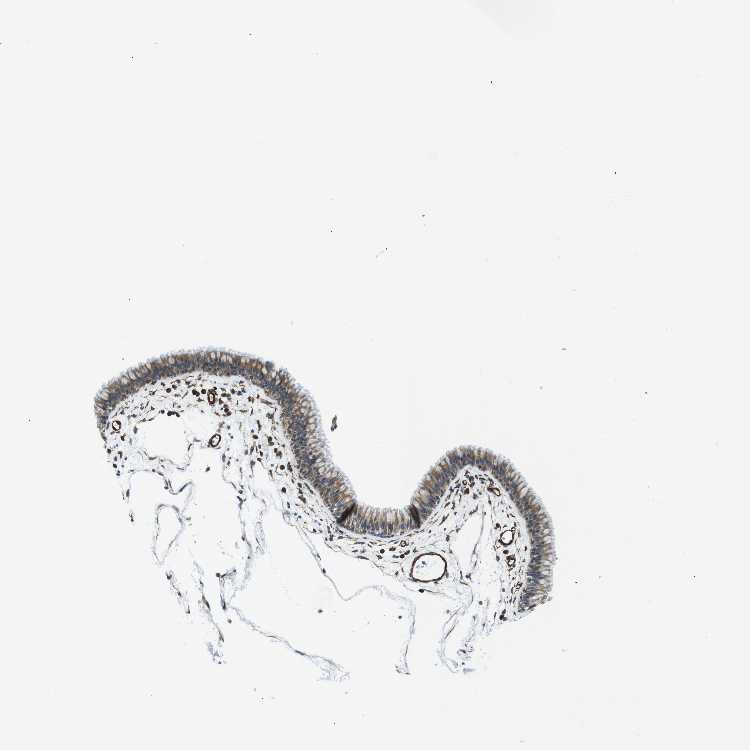

TISSUE PRIMARY DATA NASOPHARYNX Show tissue menu

NASOPHARYNX - Antibody stainingi

Antibody staining in the annotated cell types in the current human tissue is reported as not detected, low, medium, or high, based on conventional immunohistochemistry profiling in selected tissues. This score is based on the combination of the staining intensity and fraction of stained cells.

Each image is clickable and will lead to virtual microscopy that enables deeper exploration of all samples and also displays staining intensity scores, fraction scores and subcellular localization as well as patient and tissue information for each sample.

Antibody HPA015988

Respiratory epithelial cells Medium